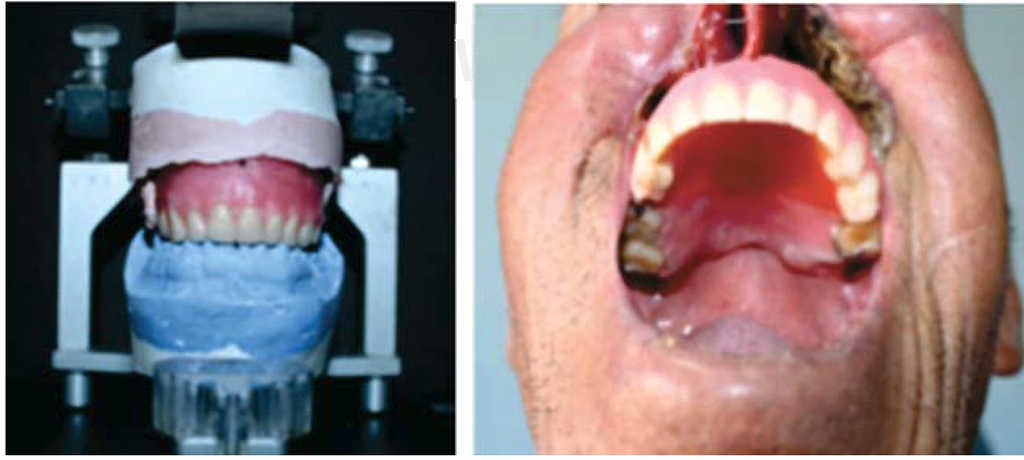

Después de hacer las pruebas estética, fonética y protésica, se continúa con el resto de relaciones craneomandibulares; para lo cual el articulador es fundamental para establecer una correcta relación y función de los modelos de trabajo del paciente de acuerdo con las bases fundamentales de la prostodoncia total (Figura 2).